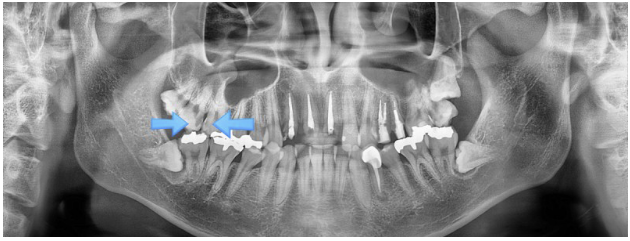

환자분께 치아 상태와 예후를 자세히 설명드린 후, 치아 상태가 좋지 않아 발치를 원하신 덕분에 임플란트 시술을 진행하기로 결정하였습니다.

오른쪽 사진에서 보이는 다른 치아들은 신경치료로 치료를 마무리했습니다.

무엇보다 정기적인 치과 검진을 통해 적절한 관리 시기를 놓치지 않는 것이 중요합니다.

이미 통증이 발생한 뒤 내원하게 되면 치료가 늦어질 수 있기 때문에, 미리 예방을 위해 전문가의 도움을 받는 것을 권장드립니다. 감사합니다.